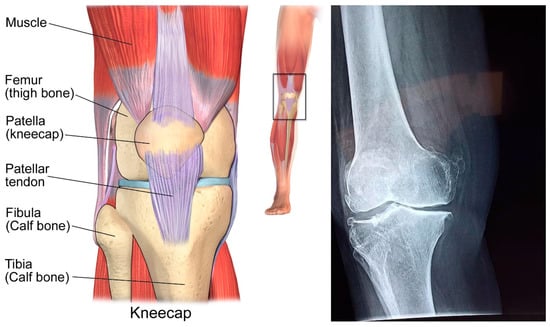

1.1. Structure of Human Knee